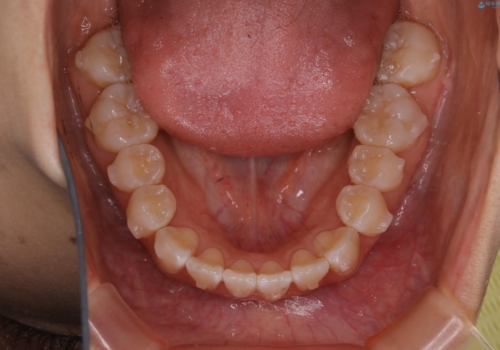

前歯のがたつきとオープンバイト:インビザラインでまとめて治す

- 噛み合わせと、前歯のがたつきが気になるとご相談にいらした方です。インビザラインFULLで綺麗な歯並びと噛み合わせを作ることが出来ました。

オープンバイトの方への治療は、通常抜歯を行いワイヤーによる矯正治療を行うことが多いですが、今回はインビザラインの特性を生かし、非抜歯にて綺麗な歯並びを作ることが出来ました。

舌癖がある方は、歯を内側から押し出す力が日常的に働くため、矯正治療後も歯と歯の隙間が開いてしまうなどの後戻りのリスクが高いことが知られています。舌の正しいポジショニングやお口周りの筋肉のトレーニングを行うことで後戻りのリスクを減らすことが可能です。